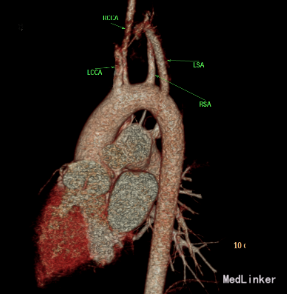

心脏CT:内脏、心房正位,左位心。肺动脉瓣二叶瓣,左室发育好。McGoon指数3.9。左室容积指数69.6ml/㎡。干下室间隔缺损,缺损约21.8mm。右位主动脉弓。迷走左锁骨下动脉。左锁骨下动脉异常起源于降主动脉起始处,经食管后方走行至左侧。左、右冠状动脉起源、走行未见异常。纵隔内未见体肺侧支动脉。气管下段中度狭窄。

诊断:先天性心脏病 Fallot四联症 心功能II级 迷走左锁骨下动脉

患者因Fallot四联症行术前常规检查,发现合并迷走左锁骨下动脉。临床上迷走右锁骨下动脉比较多见。此患者右位主动脉弓。迷走左锁骨下动脉。左锁骨下动脉异常起源于降主动脉起始处,经食管后方走行至左侧。迷走左锁骨下动脉有二种类型:一种为单纯迷走锁骨下动脉,,一种同时合并Kommerell憩室。可能以22q11.2缺失有关。迷走左锁骨下动脉与双主动脉弓一样,是可以完整形成血管环的畸形。迷走左锁骨下动脉常合并有Fallot四联症、室间隔缺损等心脏畸形。心脏增强CT或核磁共振有助于左迷走锁骨下动脉诊断。通常没有食道、气管等脏器的压迫,不需要手术矫正。